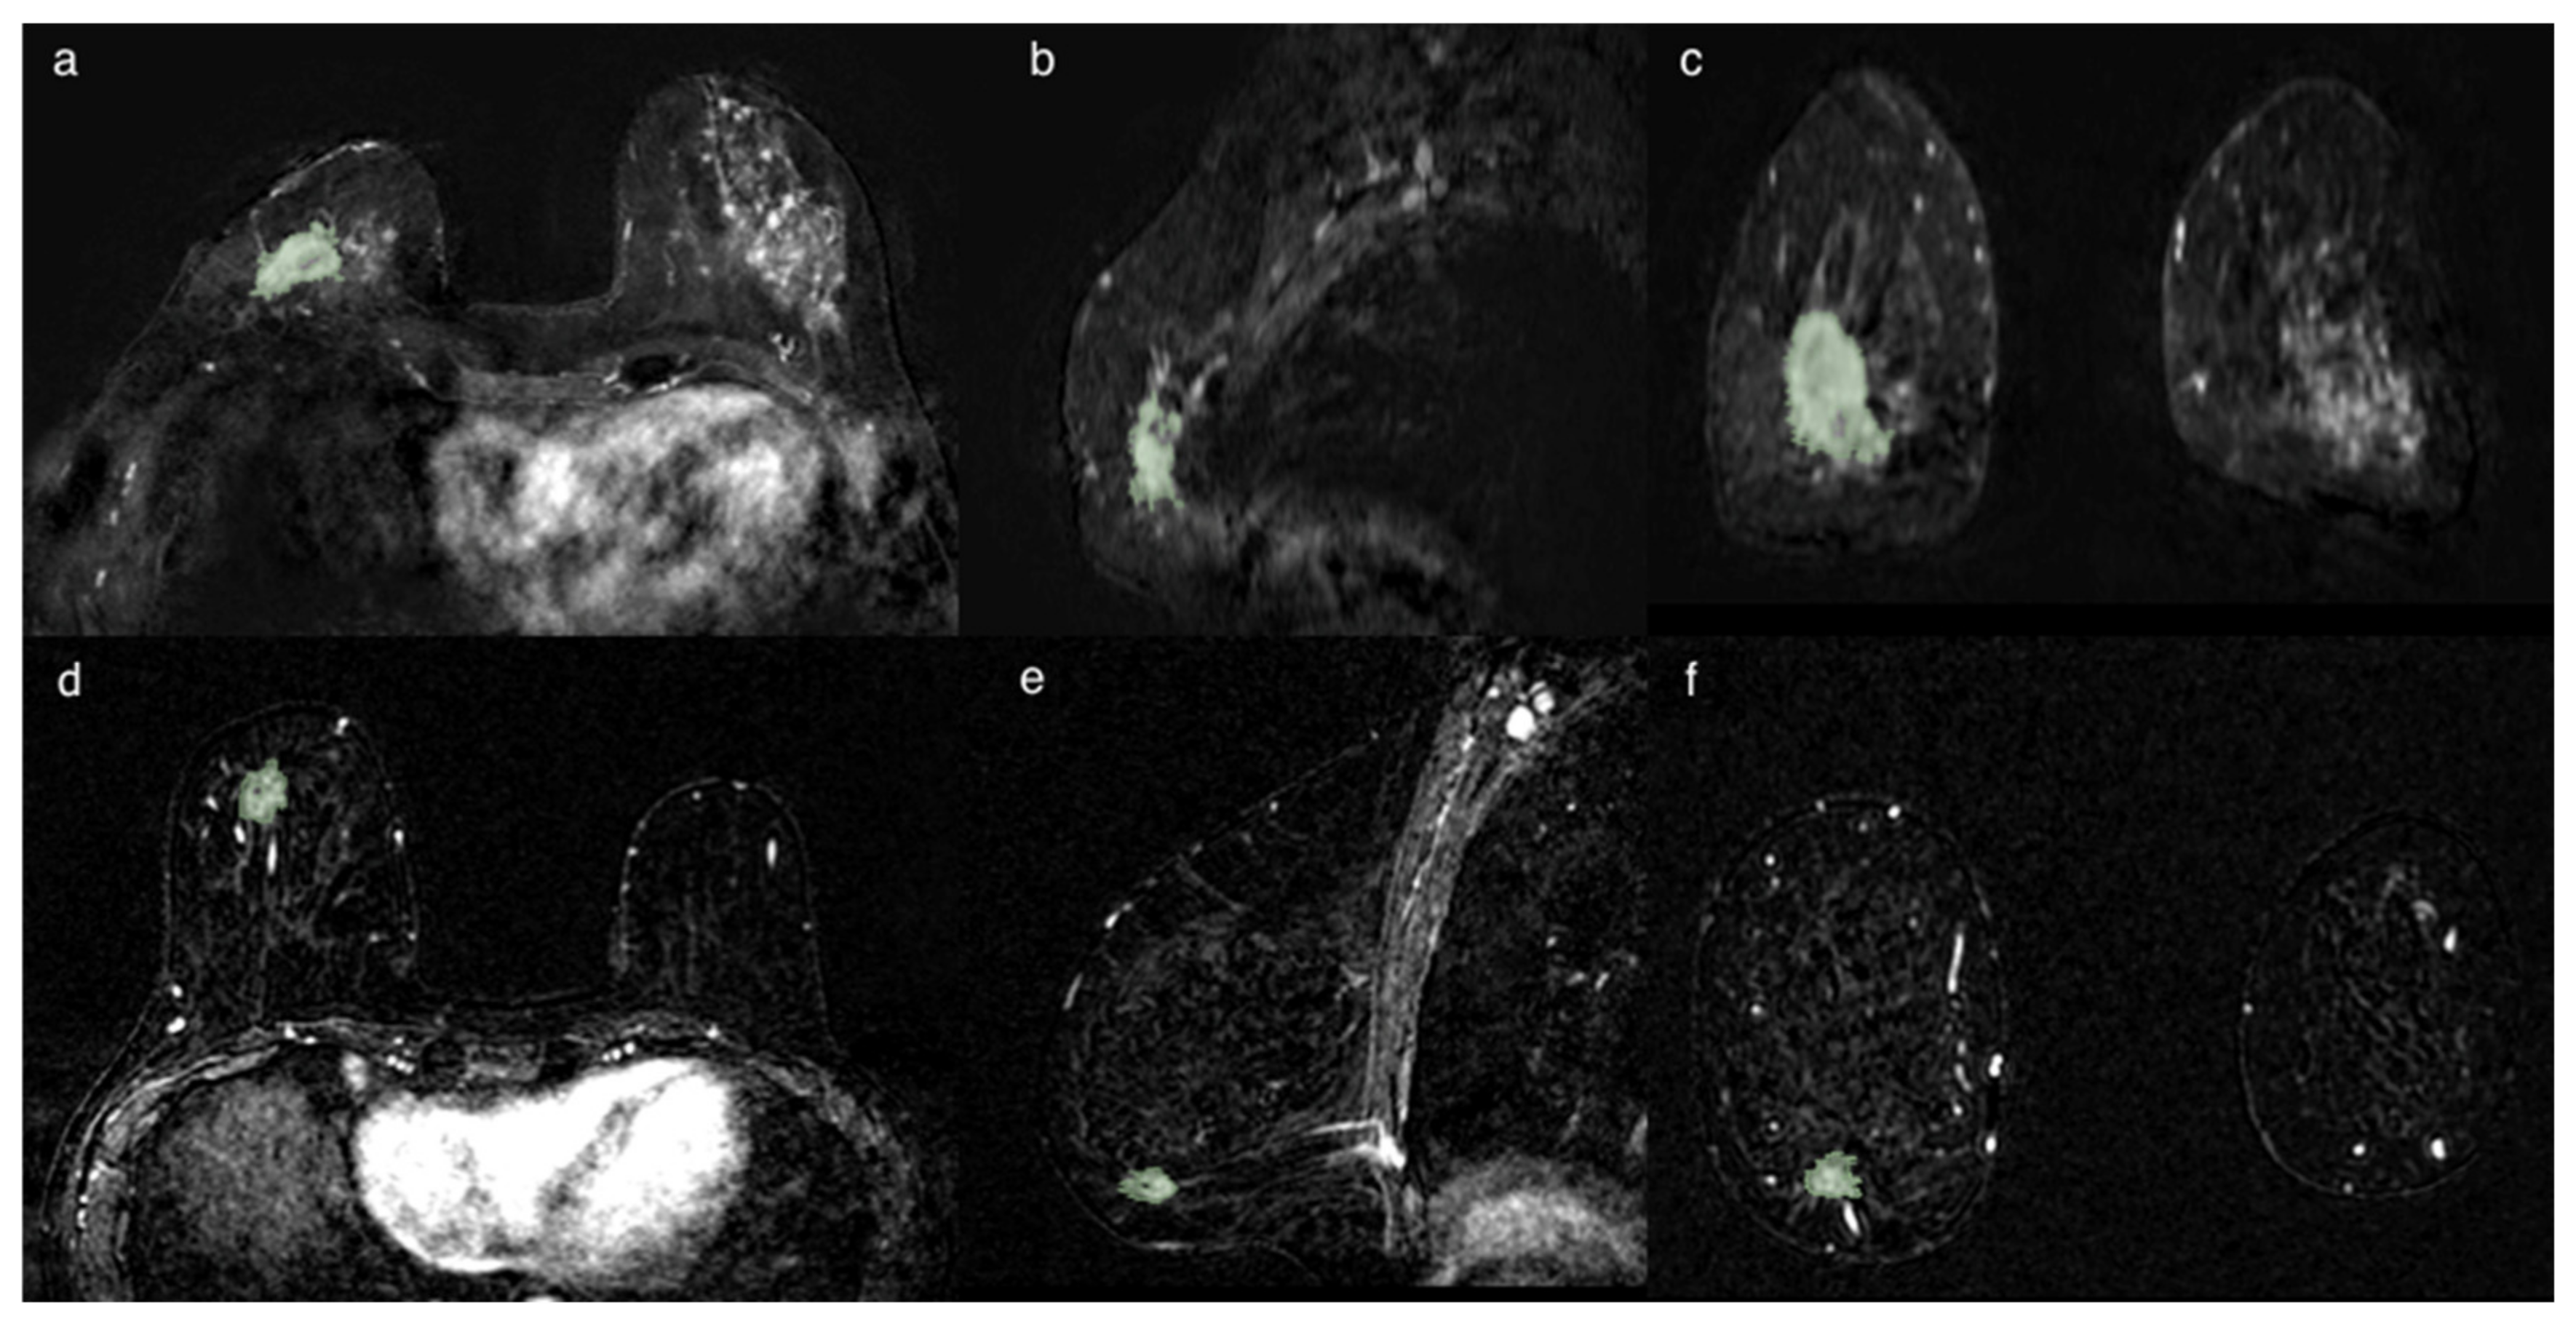

The segmentation was initially always performed in the axial projections and subsequently remodeled and optimized in the other projections until the lesion was contoured optimally, avoiding the necrosis when present into the lesion, as shown in Figure 3.

Figure 3. Two cases of breast cancer with positive and negative lymph node axillary involvement at definitive surgery, respectively. The first (ac) represented by a 32 mm mass, in 56yo patient with TN CDI tumor characterized by spiculated margins, heterogeneous enhancement with a necrotic core and a signal/intensity curve type 3 at MRI exam. The second (df) is a 13 mm nodule, in a 61 yo patient, LUMINAL A CDI, characterized by irregular margins, heterogeneous enhancement and a signal/intensity curve type 3. The segmentation has been performed in the axial image (a,d), following the margins and including the spicule characterized by contrast-enhancement. The segmentation was then optimized in the sagittal (b,e) and coronal (c,f) planes, avoiding the darker part representing the necrosis and the vessels.